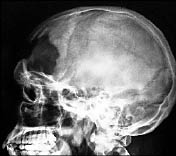

Несколько суток Павел Курганский находился в коме, балансируя между жизнью и смертью. Перенес несколько операций. Ему удалили правый глаз, произвели трепанацию черепа, заменили часть лобной кости на пластик. С самого начала врачи диагностировали ушиб головного мозга тяжелой степени, размозжение лобной доли мозга, множественные переломы костей черепа и правой гайморовой пазухи носа. Павел выжил, но в 21 год стал инвалидом.

Павлу КУРГАНСКОМУ (на верхнем снимке) удалили правый глаз, произвели

трепанацию черепа, заменили часть лобной кости на пластик.